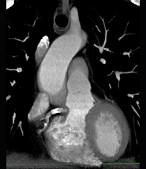

下面一组图像应考虑为 ( )A、左前降支钙化B、左旋支钙化C、正常的左前降支D、右侧冠状动脉钙化E、正常的右侧冠状动脉